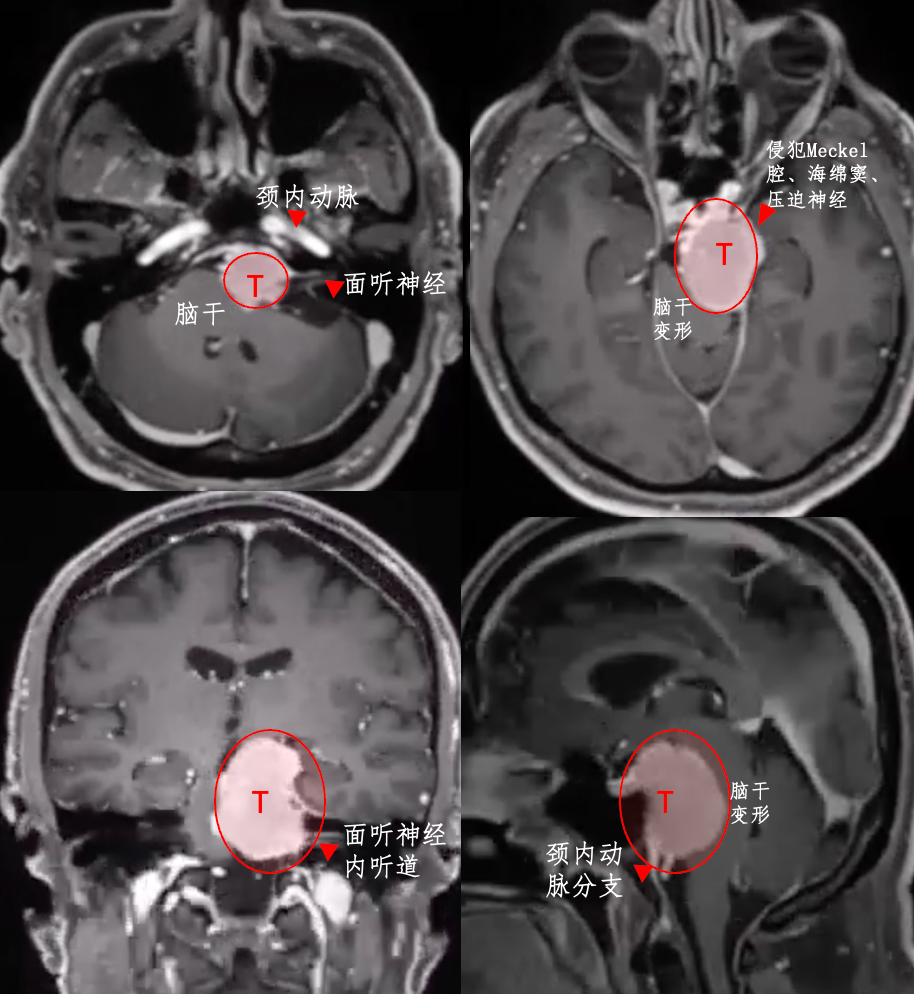

先来看看这个案例,29×39×38 mm,一个大型岩斜区脑膜瘤像一个小山丘一样,山顶直接挤压“生命禁区”脑干,还与神经血管结构紧密粘连。此时的他仅有头痛症状。

要知道,岩斜区这个位置的脑膜瘤,大小每增加1cm,手术难度就升级。位置凶险,肿瘤大,很多人以为肯定得开颅才能切干净。

其实不然,在INC福教授的定制化手术策略之下,无需开颅,仅右侧单鼻孔入路便全切肿瘤。脑干复位良好,未见脑脊液漏及新发神经功能障碍。

54岁男性Bruno,也是岩斜区脑膜瘤,但是他就没那么幸运了。左侧脸部如刀割般疼痛,甚至还出现吞咽困难,无法进食、难以入眠、无法工作……

2014年,查出岩斜区脑膜瘤,考虑到这是个良性肿瘤,且手术治疗有风险,他选择了保守观察。然而,6年时间,肿瘤持续增长,压迫脑干,症状不断恶化。

福教授采用开颅手术,术前通过线圈在咽升动脉处进行栓塞,可以显著减少术中出血。在切除肿瘤过程中,使用CUSA刀对肿瘤逐渐减瘤。术后MRI显示肿瘤几乎完全切除,脑干受压解除。